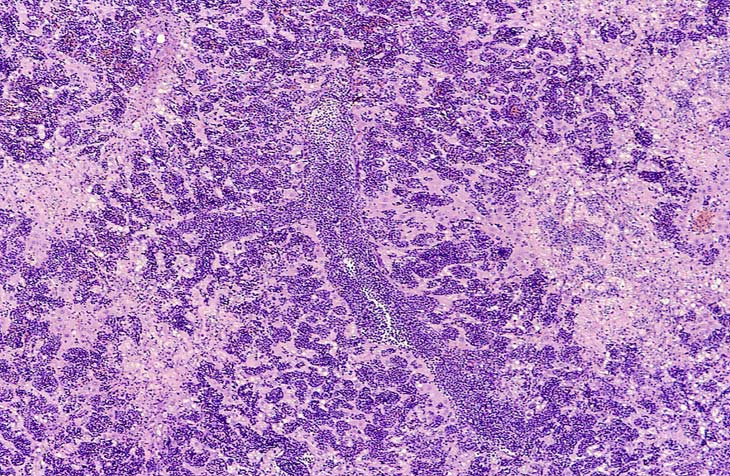

A higher magnification of hepatic erythroleukemia.

Examples of erythroleukemia in a Tg.AC mouse.